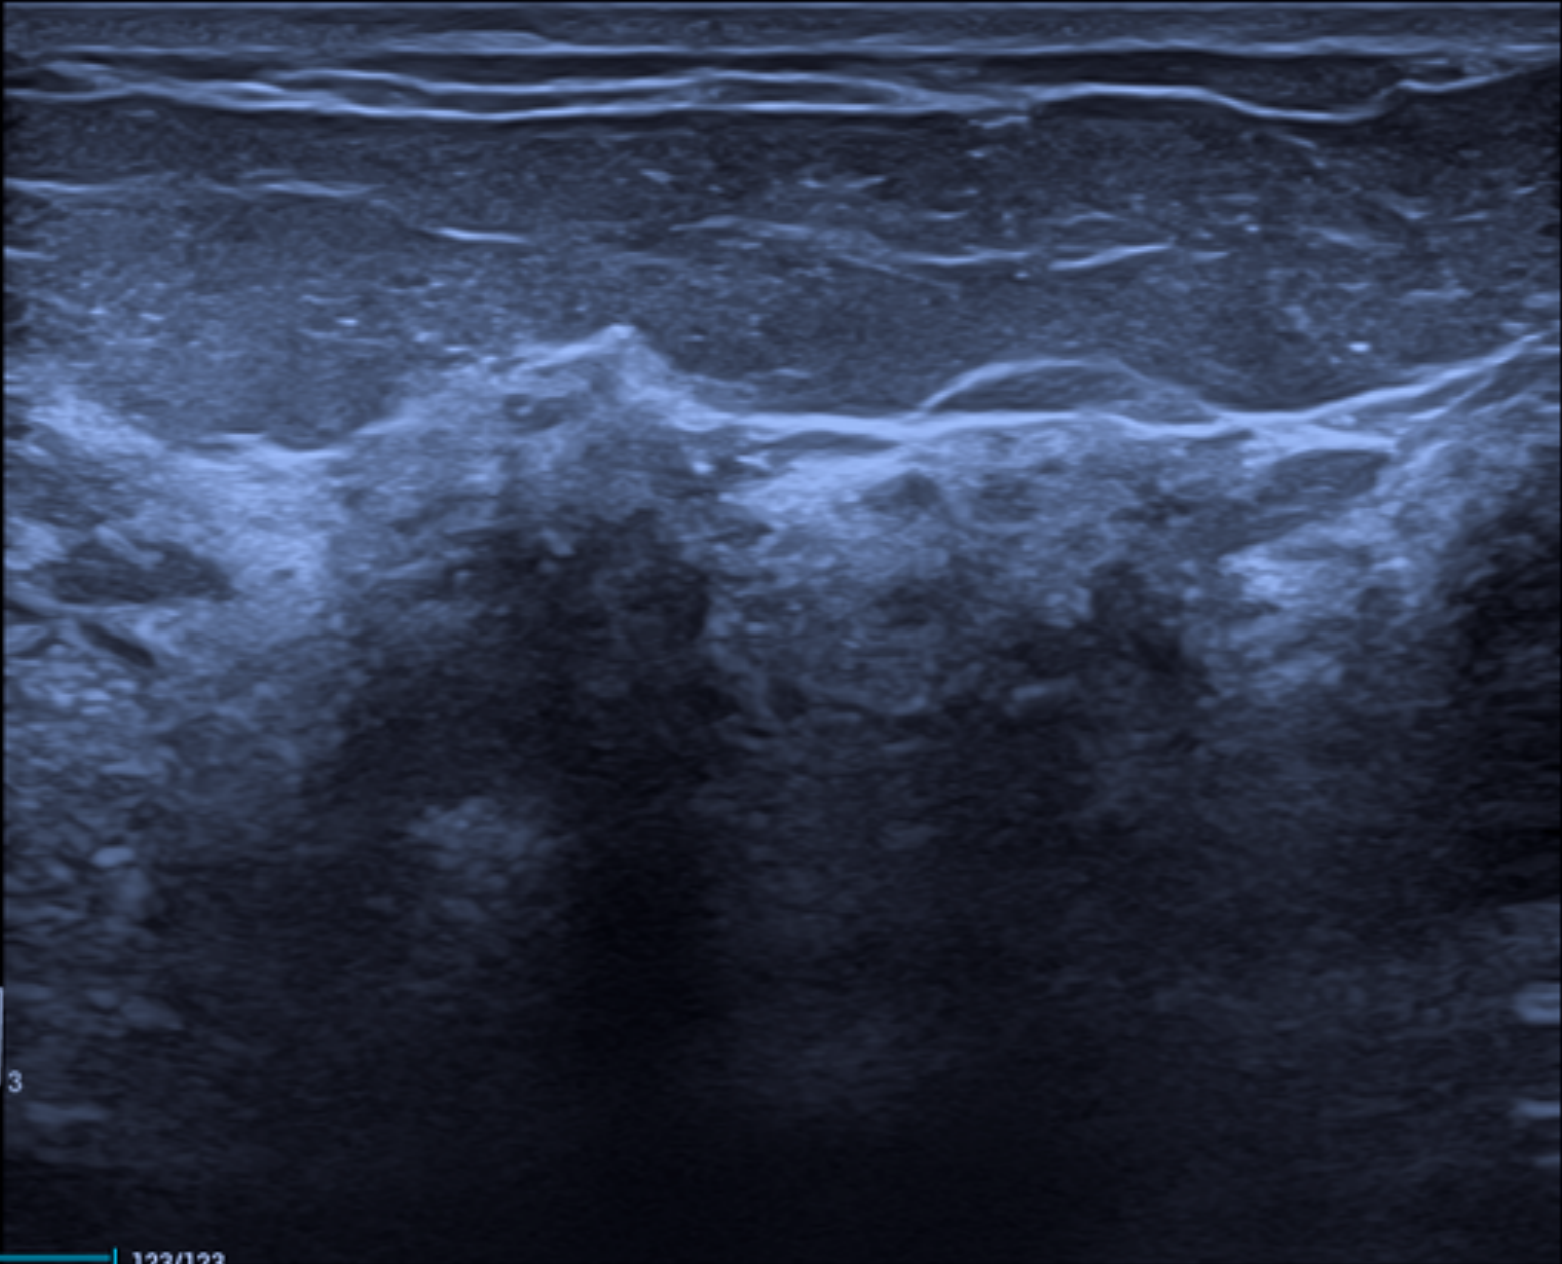

Com base na composição tecidual predominante, descrevem-se três padrões básicos de ecotextura mamária ao ultrassom, em concordância com o BI-RADS:

Ecotextura de fundo homogênea gordurosa, na qual os lóbulos adiposos e bandas ecogênicas de sustentação predominam;

Ecotextura de fundo homogênea fibroglandular, caracterizada por uma faixa espessa e relativamente homogênea de parênquima fibroglandular sob uma camada delgada de gordura subcutânea, sendo esse o local onde se concentram a maioria das lesões mamárias;

Ecotextura de fundo heterogênea, na qual áreas de gordura isoecóica se intercalam com regiões fibroglandulares hiperecóicas, refletindo maior complexidade arquitetural do parênquima.

O reconhecimento do padrão de ecotextura de fundo é essencial, pois influencia diretamente a conspicuidade das lesões, a avaliação de seus limites e a aplicação adequada dos critérios morfológicos do BI-RADS.